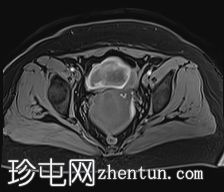

轴位

DWI序列

可见子宫外腹腔内妊娠囊,内含胎儿组织。

该妊娠囊向后推移子宫,并与剖宫产瘢痕凹陷处紧密相连。

该妊娠囊与相关肠袢无法分离。可见其与性腺血管密不可分,且性腺血管明显突出。

胎盘位于妊娠囊后方,紧贴子宫前壁。

沿妊娠囊下缘可见一处异质性局灶性积液,最大轴向尺寸约为 8.4 × 5.5 cm,T1 加权像呈异质性高信号,T2 加权像呈异质性中等信号,T1 脂肪抑制序列未见信号下降,提示为血液成分。该积液压迫膀胱。

可见周围脂肪间隙呈条索状改变。

子宫体积增大,后倾,子宫内膜厚度约 1 cm,子宫下段前壁可见局灶性变薄(既往子宫瘢痕)。子宫连接区完整,未见肌层肿块。可见子宫内膜腔边缘有血性分泌物。